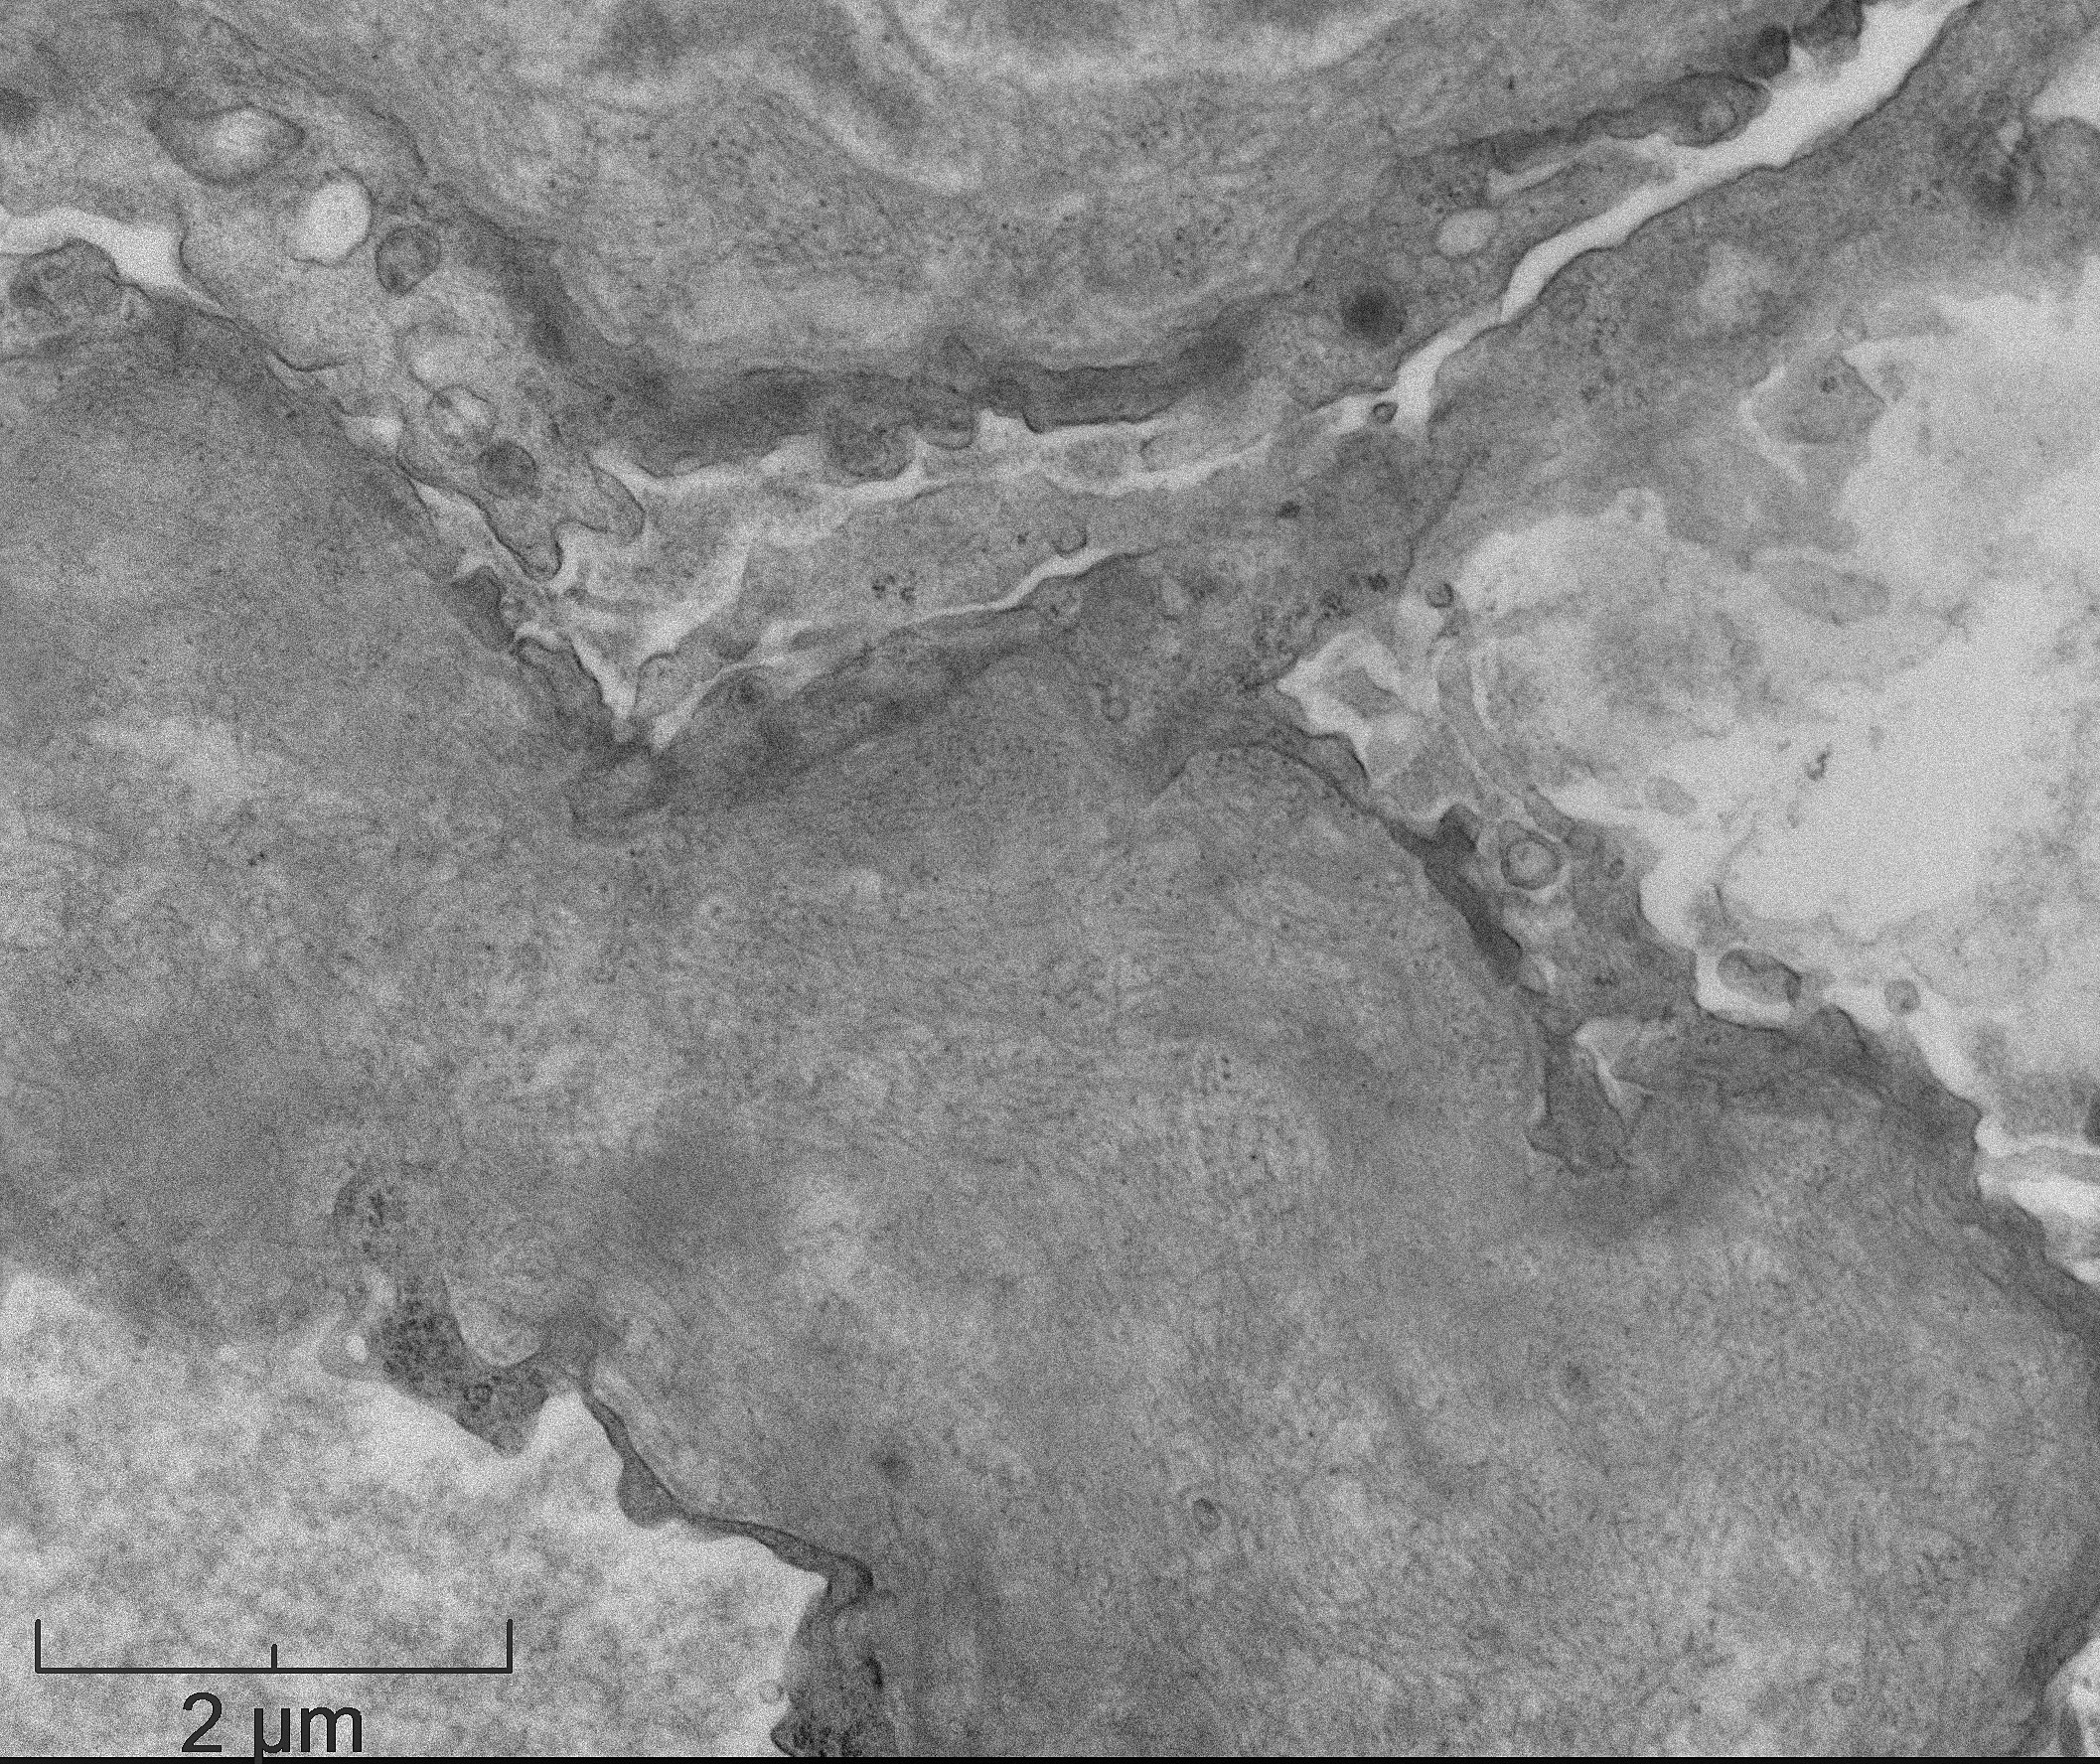

The patient is 32 year-old female with acute kidney injury and nephrotic range proteinuria. A renal biopsy showed diffuse global mesangial and capillary wall expansion by eosinophilic weakly PASH positive material (Silver stain showed in Figure 1), with cellular crescents in 40% and fibrocellular crescents in 5% of the glomeruli. A Congo red stain failed to show apple-green birefringence under polarized light (Figure 2). There was intense immunofluorescence staining with IgG, IgA, C3, and light chains (Figure 3). Electron microscopy showed fibrils with 25 nm average diameter (Figure 4).

FGN is a rare form of glomerulonephritis (less than 1% in native renal biopsies), which diagnosis is historically defined by glomerular deposits of Congo red negative, randomly arranged, straight fibrils without a hollow center that measure between 10-30 nm in diameter (larger than amyloid fibrils) and stain for immunoglobulins. The fibrils are localized in the mesangium and/or along the glomerular basement membrane.

The distinction between FGN and amyloidosis is made on the basis of Congo red, DNAJB9 (high sensitivity and specificity for FGN) and composition of fibrils by electron microscopy. Immunohistochemistry against AA amyloid may be used to diagnose a specific type of amyloid deposits. PLA2R (M-type phospholipase-A2 receptor) and THSD7A (thrombospondin type-1 domain-containing 7A) are used in the diagnosis of membranous nephropathy.